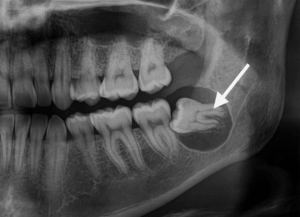

当院では、通常の二次元的なレントゲン撮影に加えて必要不可欠と判断した症例においては、必ず「歯科用CT」による撮影を行います。

歯科用CTを用いることで次のような情報を、ミリ単位で正確に把握することができます。

- 親知らずの根の形や本数、湾曲の度合い

- 顎の骨の中での親知らずの正確な位置と傾き

- 親知らずの根の先端と下歯槽神経との三次元的な位置関係

CTによる事前の詳細なシミュレーションは、手術中の偶発的な事故(神経の損傷など)のリスクを限りなくゼロに近づけより安全で確実な抜歯を可能にするための、いわば「手術の設計図」となる極めて重要なプロセスです。